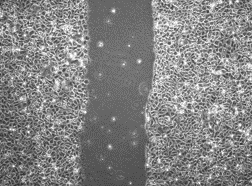

Xác minh sơ bộ PIXCELL BIOM™

Kết quả được chứng minh trong phòng thí nghiệm là nhanh hơn 56% so với lipid da trung bình *

* Kiểm tra xem độ dài ở giữa hẹp đến mức nào.

- Trước khi sử dụng chất thử nghiệm

- 12 giờ sau khi dùng chất thử

Bảng 1. Tốc độ thay đổi tế bào theo thời gian

Nội dung thử nghiệm

Sau khi dùng chất thử nghiệm cho đối tượng thử nghiệm nhận được kích thích trung tâm và quan sát trong 12 giờ, tỷ lệ thay đổi 75,8% đã được xác nhận

ở đối tượng thử nghiệm được dùng PixelBiome™ .

*Là một thí nghiệm nội bộ để giúp hiểu rõ hơn, những điều trên chỉ giới hạn ở tính chất của nguyên liệu thô.